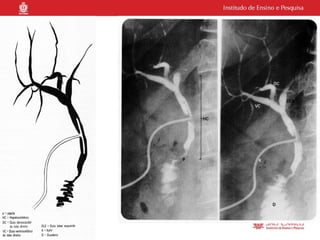

O documento descreve indicações para exames de imagem de ductos biliares, incluindo colangiografia retrógrada endoscópica para pacientes com cálculos migrados da vesícula biliar ou pacientes ictéricos. Ele também menciona radiografia piloto, uso de contraste hidrossolúvel e que o procedimento é realizado por um médico gastroendoscopista.